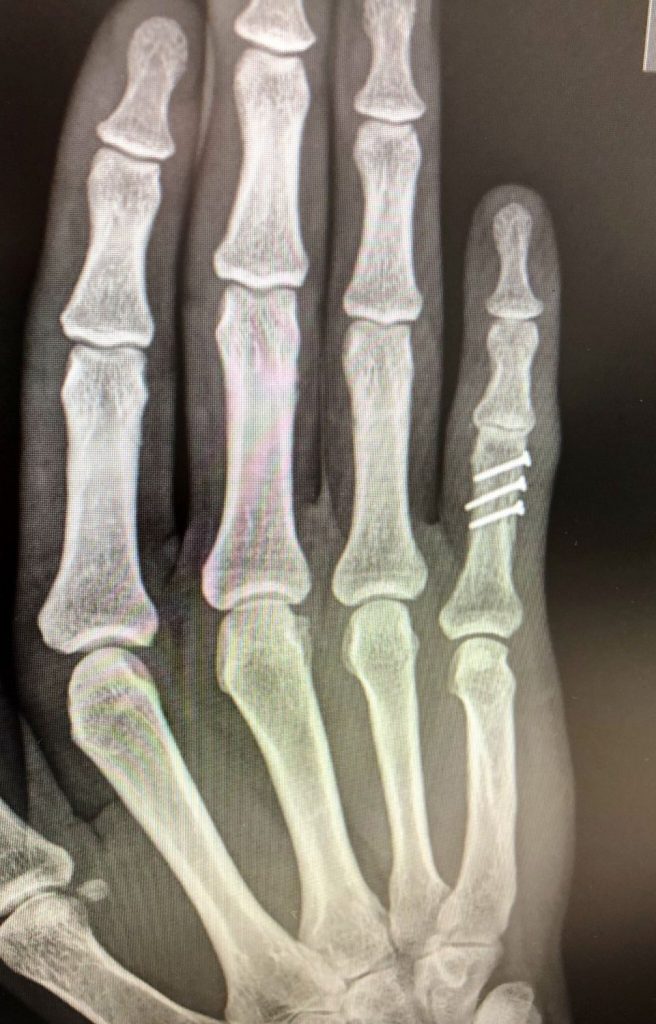

Figura 6 - Osteosíntesis con tornillos de Fractura falange 5º dedo desplazada.